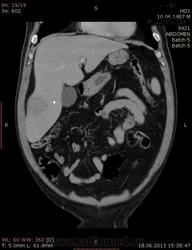

На абсцесс похоже

+1. Контраст вводили?

На мой взгляд, абсцесс.

Тоже за абсцесс.

Cпасибо , коллеги.Сегодня больного прооперировали диагноз абсцесс правой доли печени.Оказывается больной когда - то получил тупую травму живота, об этом нам не говорил.....